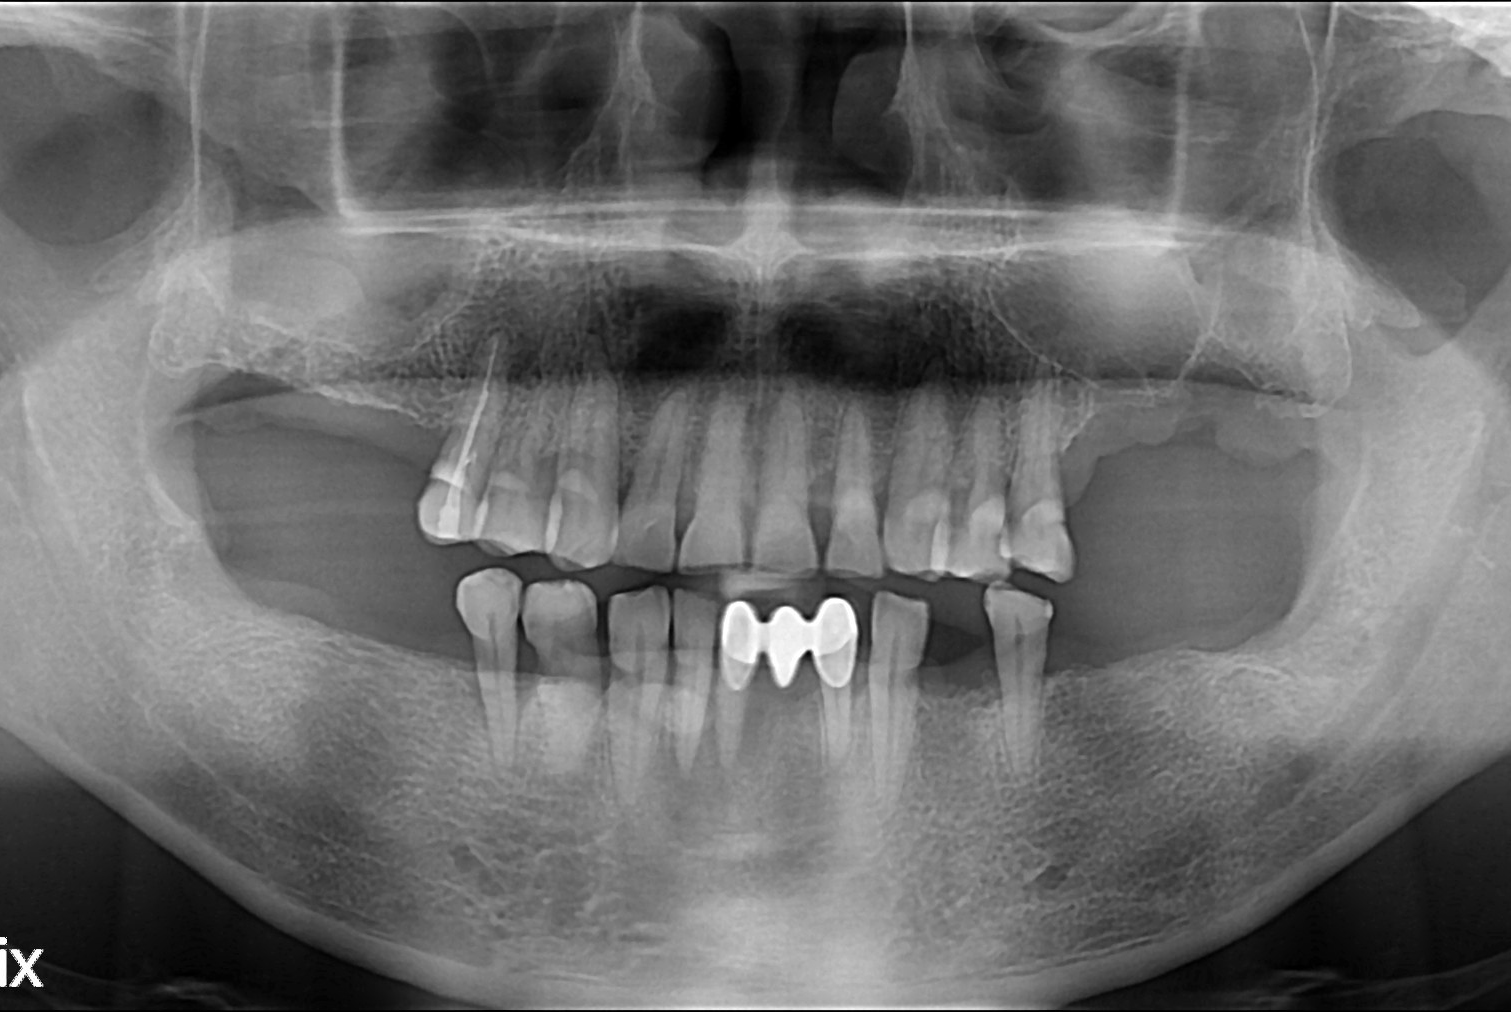

[임플란트] 임플란트

치료후 : 2017-07-06

세종치과는 많은 환자와 다양한 케이스를 바탕으로 항상 편안한 임플란트 수술을 제공하고자 노력하고,

오래동안 튼튼히 쓸 수 있는 임플란트 수술을 가장 큰 목표로 삼고 있습니다